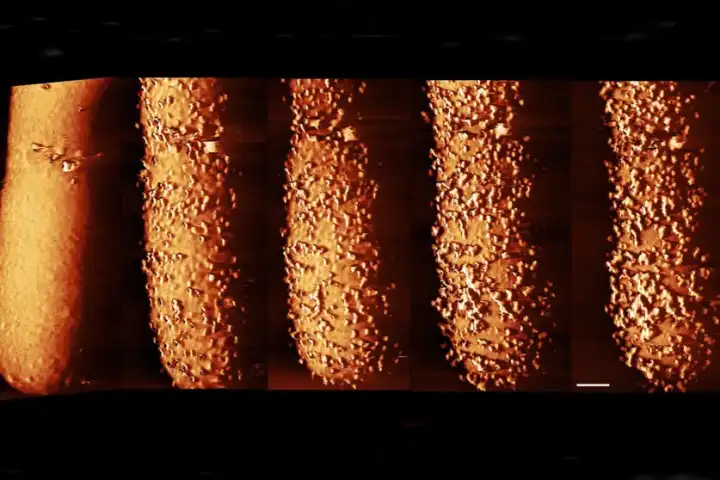

При помощи атомно-силовой микроскопии, где игла толщиной всего несколько нанометров создаёт снимки, специалисты обнаружили, что полимиксин B вызывает появление странных наростов на поверхности бактерии E. coli. Через несколько минут после появления выступов бактерия начинает быстро сбрасывать липополисахариды, оставляя бреши в своей защите, которые позволяют антибиотику проникнуть внутрь и уничтожить её.